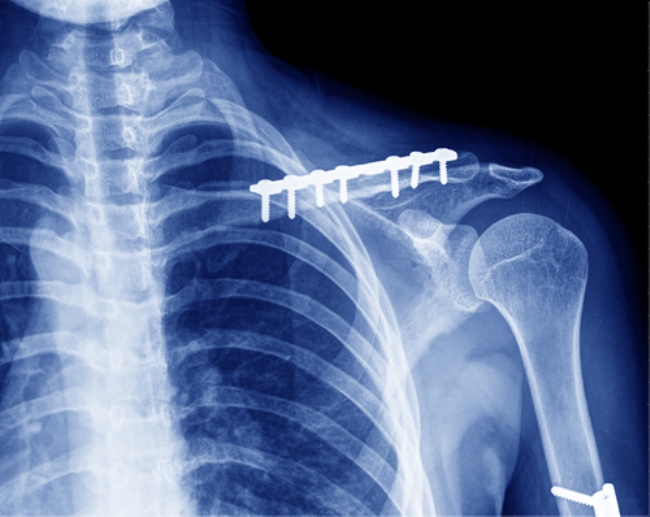

Скрепление поломанной кости ключицы с помощью пластины

Для обнаружения проблемной зоны над ключицей делается продольный разрез кожи. Травматологи убирают кровяные сгустки, совмещают костные фрагменты, накладывают пластины и фиксируют их винтами. При установке конструкций исключаются повреждения сосудисто-нервного пучка и развитие некрозов. Рана ушивается, закрывается стерильной повязкой, накладывается дренаж. Спустя 8-12 недель установленная конструкция удаляется. В некоторых случаях в этом нет необходимости.